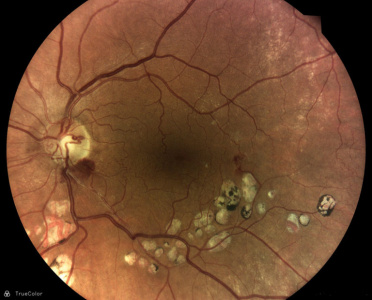

AI (umělá inteligence) okamžitě rozpozná práznaky diabetické retinopatie a klasifikuje výsledky podle závažnosti na základě mezinárodních klasifikací. Získáte přehled s hodnocením závažnosti záchytu, kde po analýze snímků zachycených kamerou iCare DRS Plus je automaticky generován report o pacientovi se stupnicí závažnosti pro diabetickou retinopatii na základě mezinárodních standardů (ICDR, AREDS).

Fundus kamera iCare DRSplus pořídí celkem 4 vysoce kvalitní True Color snímky (dva z pravého a dva z levého oka), které se automaticky ukládají na cloud a posílají se na zpracování AI - umělé inteligenci. Report je dostupný ihned a ten je možno konzultovat s pacientem během téže návštěvy u lékaře.